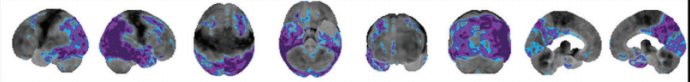

frontotemporal dementia